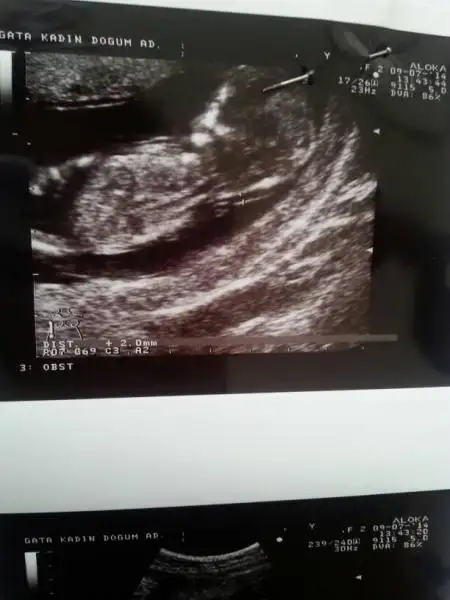

Resimleri ekte. Doktor bi tahminde bulundu, bakalım sizlerin yorumu ne olacak. Normalde 11+5 ama 12+1 olarak gözüküyor.

Kizlar oniki haftalikken cekildi bunlar su anda 16 oldum hala soylemedi doktor.gorememis bakalim siz gorebilcek misiniz?

Bildigin pipi:))